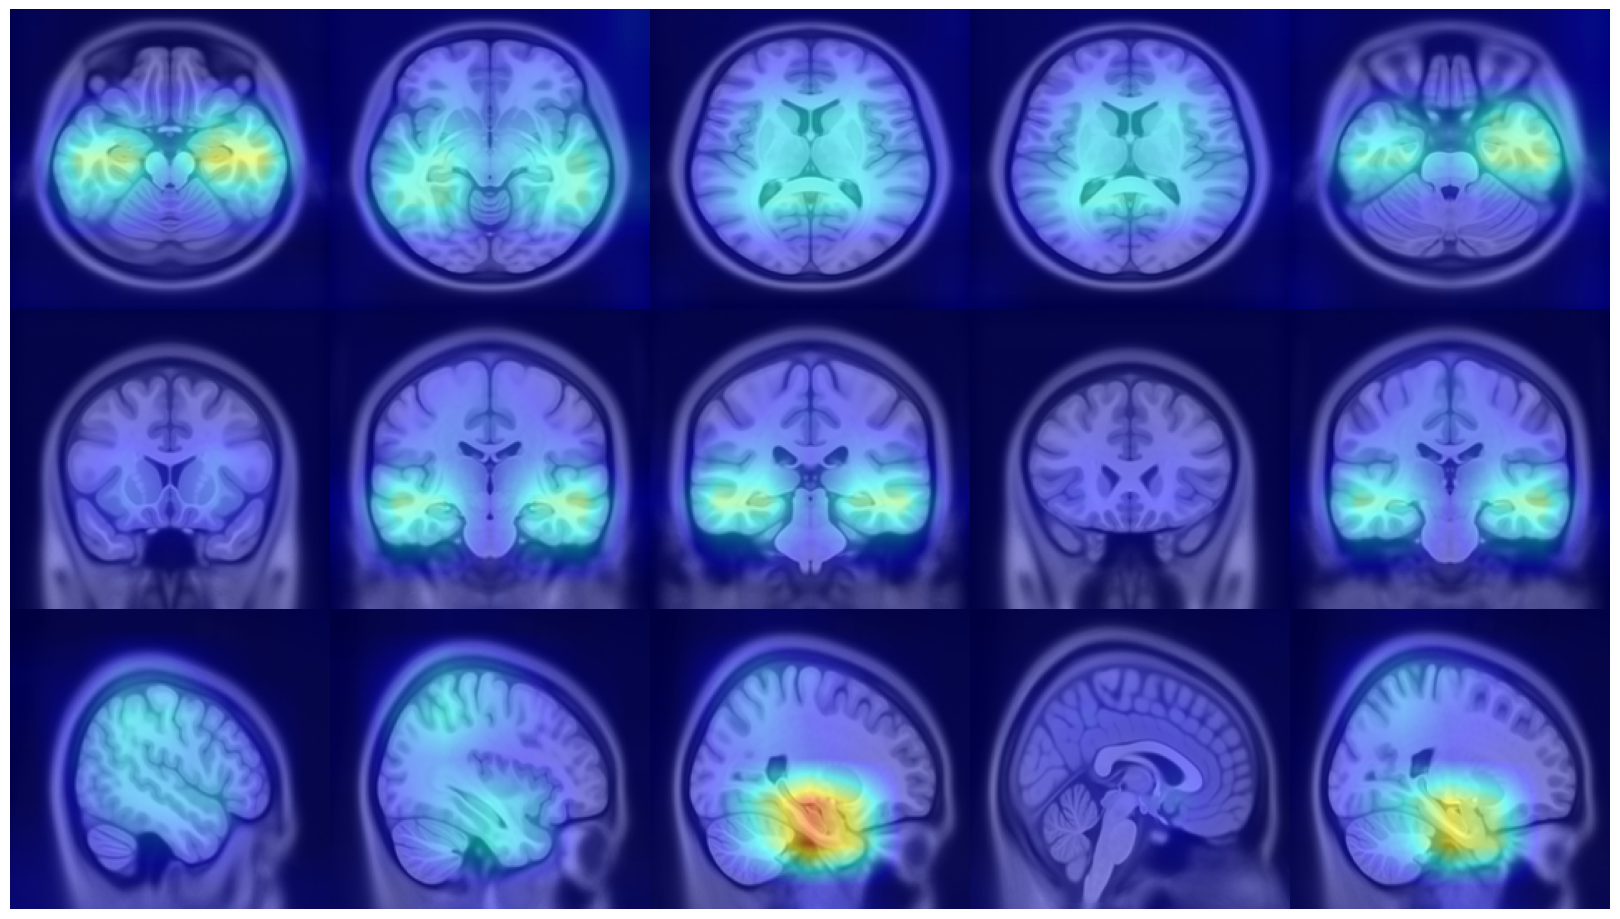

(a) Axial

(b)

(c) Coronal

Refer to caption

(d) Fold 1

(e) Sagittal

(f)

(g)

(h) Fold 2

(i)

(j)

(k) Fold 3

(l)

(m)

(n) Fold 4

(o)

(p)

(q) Fold 5

(r)

Figure 5: Average attention weight distributions generate by our model for each fold and each plane

This section analyzes the interpretability of our approach and those proposed in (Wang et al., 2024; Altay et al., 2021). Our XAI method described in Section 4.3 allowed us to produce a 3D attentional map starting from the attentional weight distributions of the axial, coronal, and sagittal planes. The authors of AwareNet (Wang et al., 2024) designed the slice-aware module of this network to extract, as in our case, a distribution of attentional weights capable of summarizing the importance of each slice in the decision-making process. As a result, our approach can produce a 3D map also using the model proposed in (Wang et al., 2024).

Many studies focused on model interpretability by generating saliency maps for randomly chosen test subjects, enabling local qualitative analysis. However, this approach does not support the evaluation of interpretability consistency when the training and testing data vary. To examine this consistency in our approach, we considered the variability of attentional weight distributions across the five different folds used for cross-validation. Our evaluation leverages a clinical hypothesis specific to AD, which is believed to affect similar brain areas across different patients. For each fold, we calculated the weight distributions for each sample in the test set and derived an average distribution specific to that test set. By analyzing these average distributions across the five folds, we could assess whether our interpretability remained consistent, thereby supporting the generalizability of our findings across different subsets of data.

Fig. 5 presents our diagnosis network’s average attentional weight distributions for each fold in the axial, coronal, and sagittal views. Upon examination of the histograms for each view, we observe a remarkable consistency in the distribution shapes across all five folds, indicating that our interpretability approach is stable despite the variation in the train/test set data. Specifically, the axial distributions reveal a consistent concentration of attentional weights around the initial slices. This trend suggests the model’s recurrent focus on the brain’s inferior regions, notably the areas where degenerative changes first manifest in AD, such as the hippocampus. In the coronal view, attentional weights are notably centered, indicating that the model consistently identifies the central part of the brain as significant. This central focus might correspond to the medial temporal lobe, including the hippocampus and the surrounding regions, further substantiating the axial findings. The sagittal view is the only bimodal distribution, suggesting that the model pinpointed symmetrical areas along this plane. We hypothesize that the network was focusing on the hippocampus since it adheres to all the constraints: situated in the inferior part of the brain, centrally located, and symmetrical. The consistency and specificity of these findings across multiple data folds strengthen the argument that our network could reliably identify specific brain regions as a critical biomarker for distinguishing between AD and CN subjects.